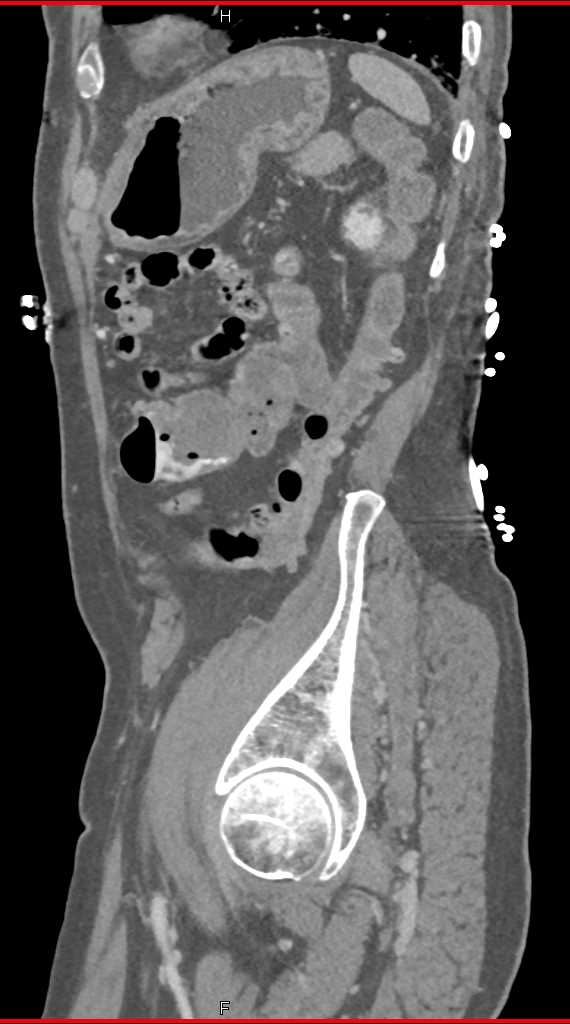

Pseudomembranous Colitis with Ascites